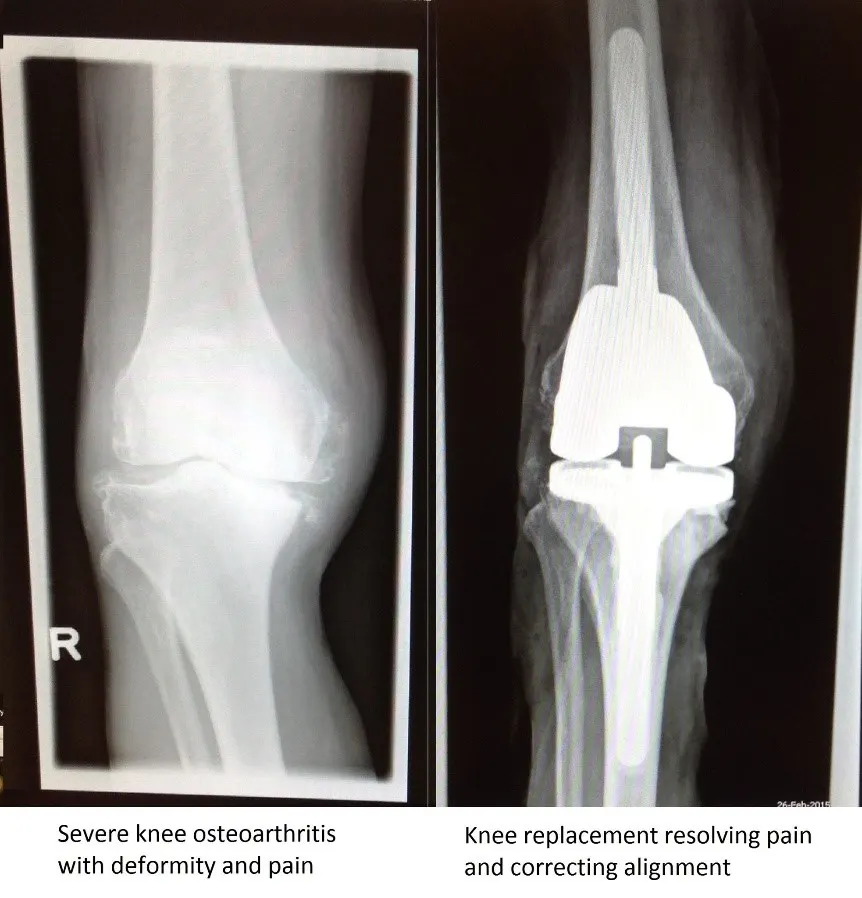

Seorang pasien lanjut usia yang hasil rontgennya ditunjukkan di bawah ini telah menggunakan kursi roda selama sekitar satu tahun akibat nyeri berat dan kelainan bentuk pada lutut kanan. Setelah memutuskan untuk menjalani operasi, pasien tersebut menjalani operasi penggantian lutut. Karena deformitas yang cukup berat, digunakan prostesis berukuran lebih besar dengan batang logam tambahan. Prostesis ini lebih besar dibandingkan prostesis standar. Secara umum, menunda pengobatan dapat membuat operasi menjadi lebih kompleks dan memerlukan prostesis yang lebih besar. Setelah operasi dan fisioterapi, pasien kini dapat berjalan di luar rumah dengan bantuan tongkat, yang merupakan peningkatan signifikan terhadap kualitas hidupnya. Kualitas hidup keluarga pasien juga ikut membaik karena pasien kembali memperoleh kemandirian.